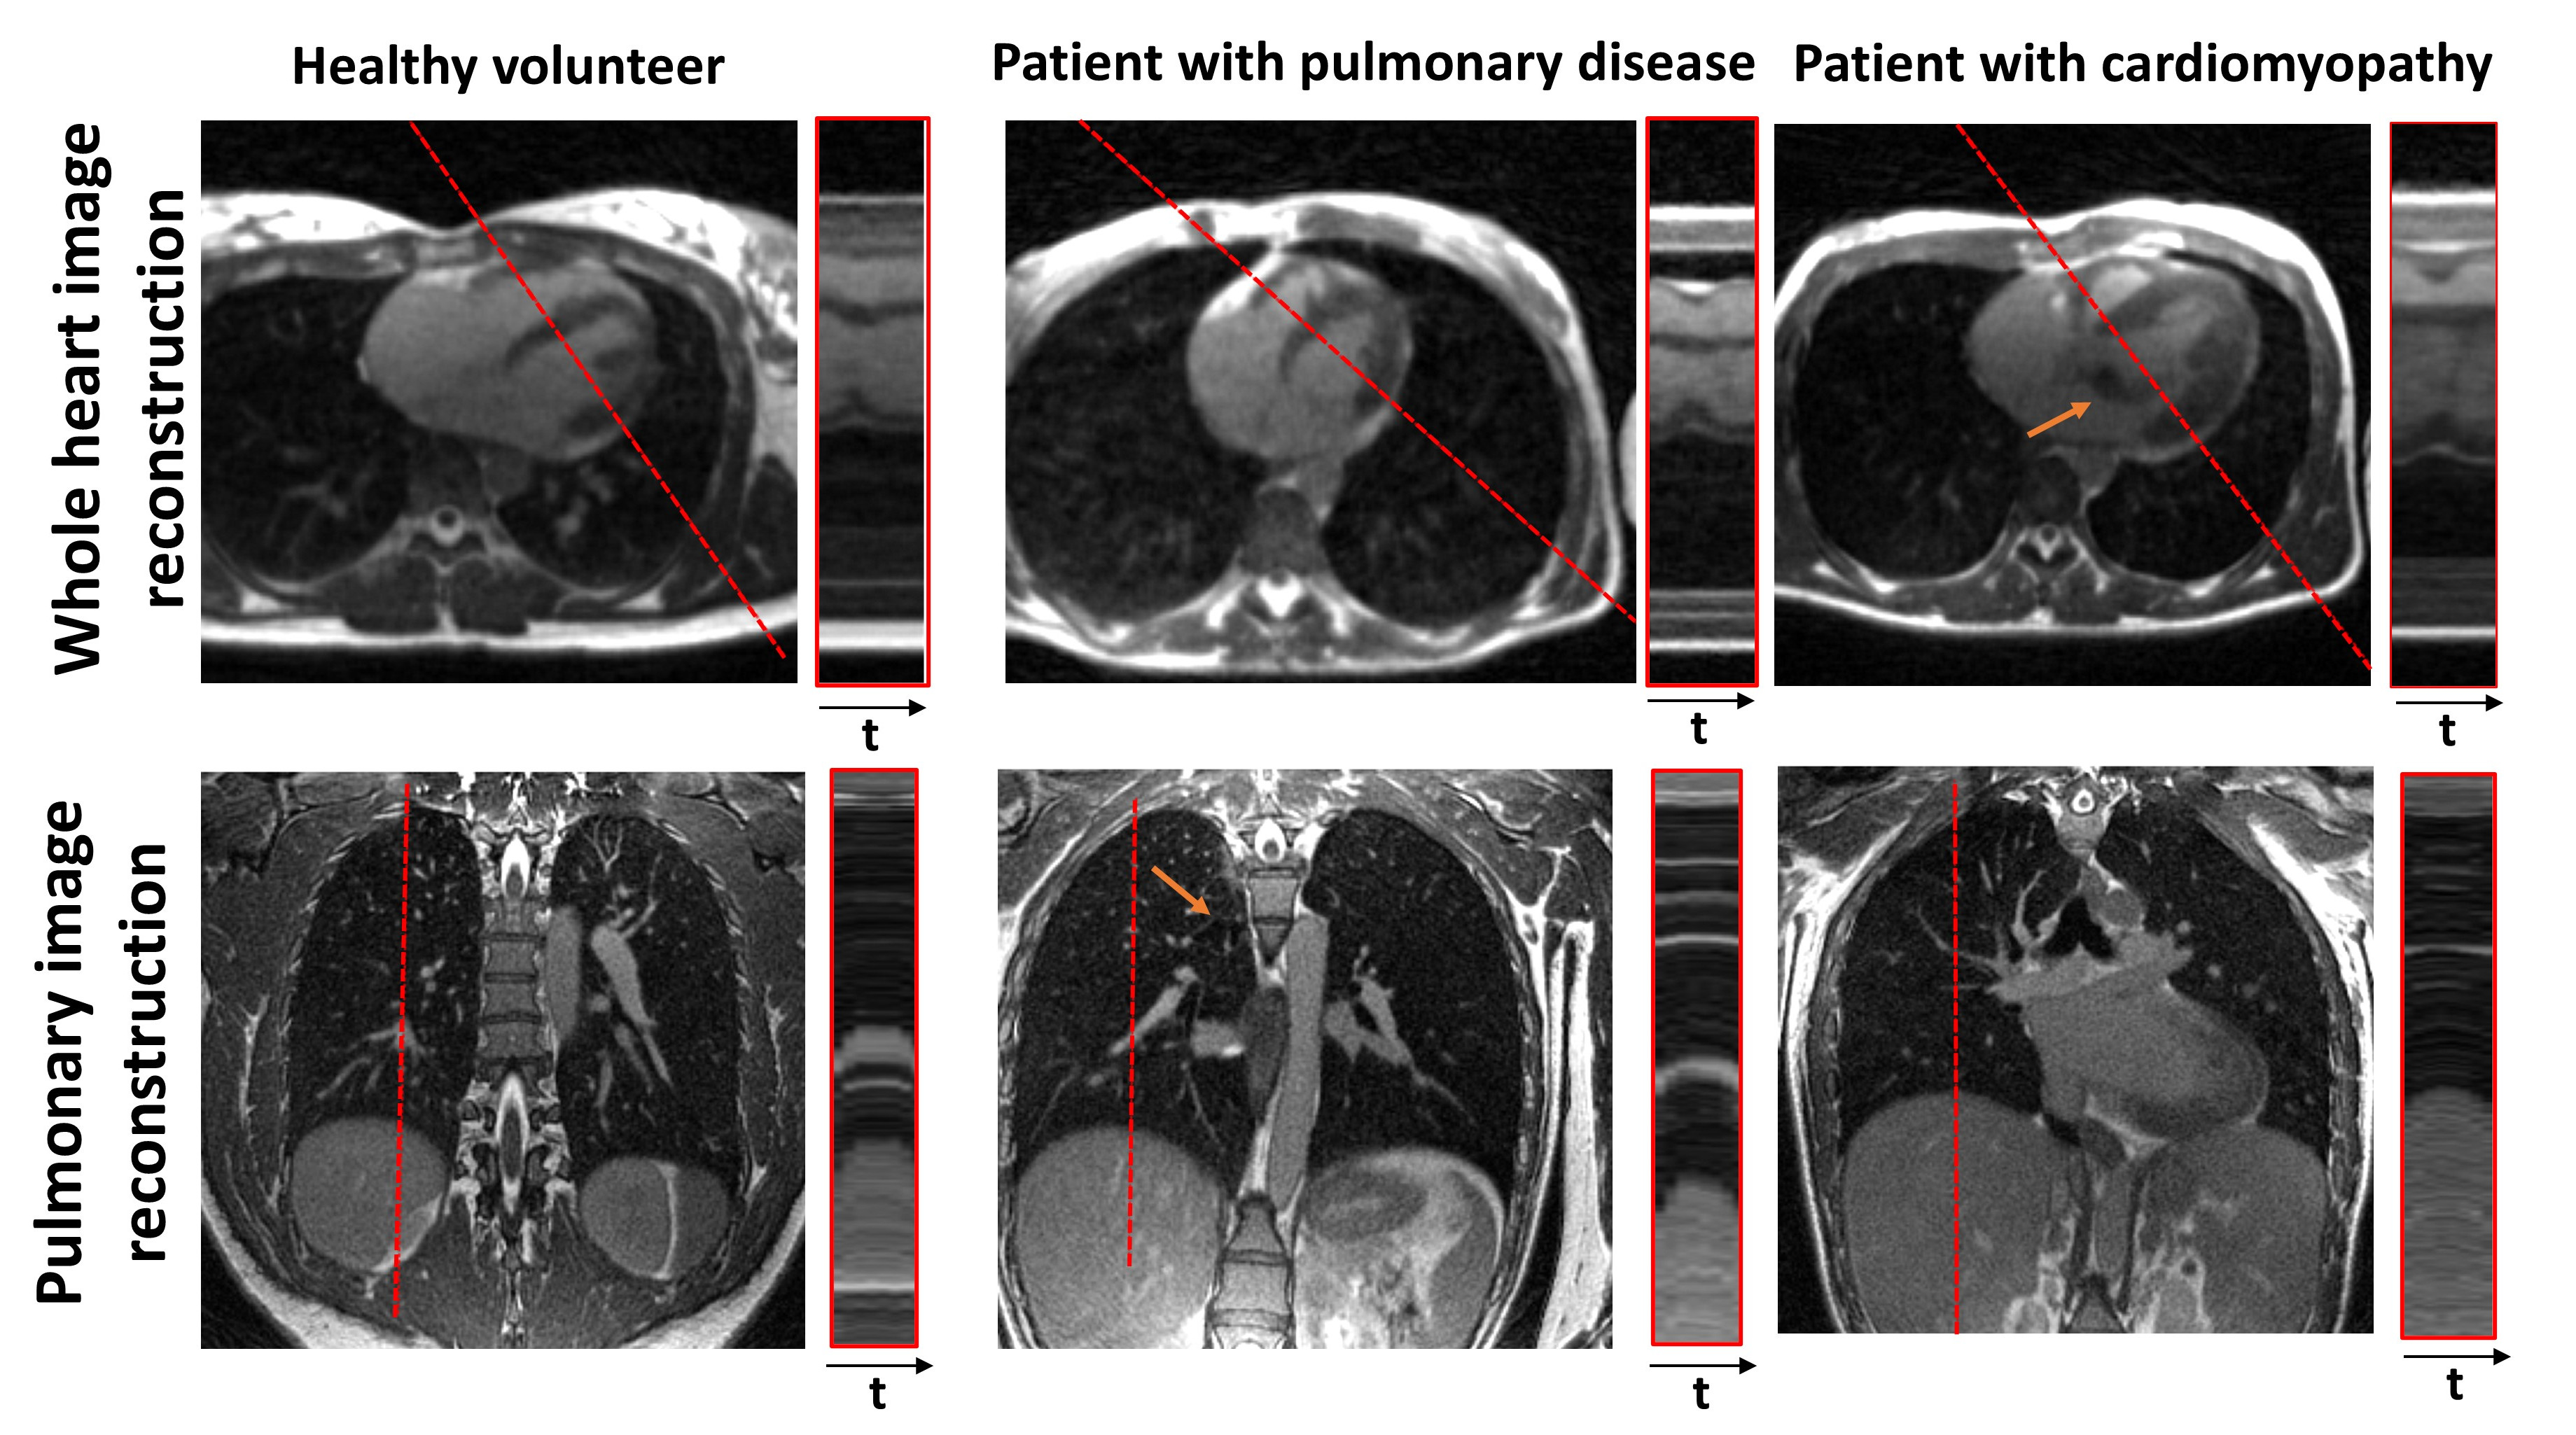

Figure 2: Cardiac and respiratory resolved images in a healthy volunteer, lymphangioleiomyomatosis patient and a patient with cardiomyopathy. Red line profiles show the temporal resolution of cardiac images (30ms) or pulmonary images (N= 8 bins). Orange arrows show the pulmonary (nodules) or cardiac (aortic regurgitation) defects.